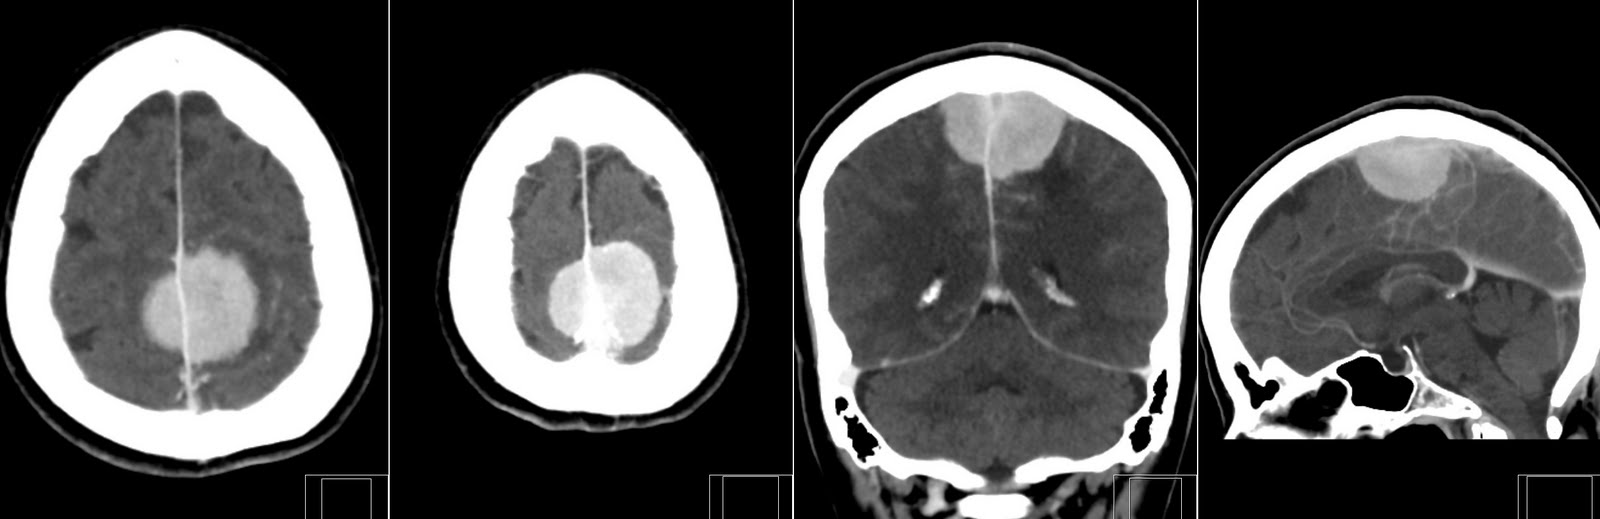

Τα μηνιγγιώματα διαγιγνώσκονται εύκολα με CT, MRI με γαδολίνιο και αρτηριογραφία.

Οι όγκοι έχουν χαρακτηριστική εμφάνιση στην MRI με ομοιόμορφη ενίσχυση του σκιαγραφικού κατά μήκος της μήνιγγας και διακριτή απεξάρτηση από το εγκεφαλικό παρέγχυμα. Η ενίσχυση του σκιαγραφικού από τη μάζα είναι γνωστή σαν μηνιγγική ουρά-dural tail και είναι χαρακτηριστικό εύρημα, αλλά δεν υπάρχει σε όλες τις περιπτώσεις.

Μπορεί να συνυπάρχει και οίδημα παρεγχύματος λόγω της πίεσης από την μάζα.